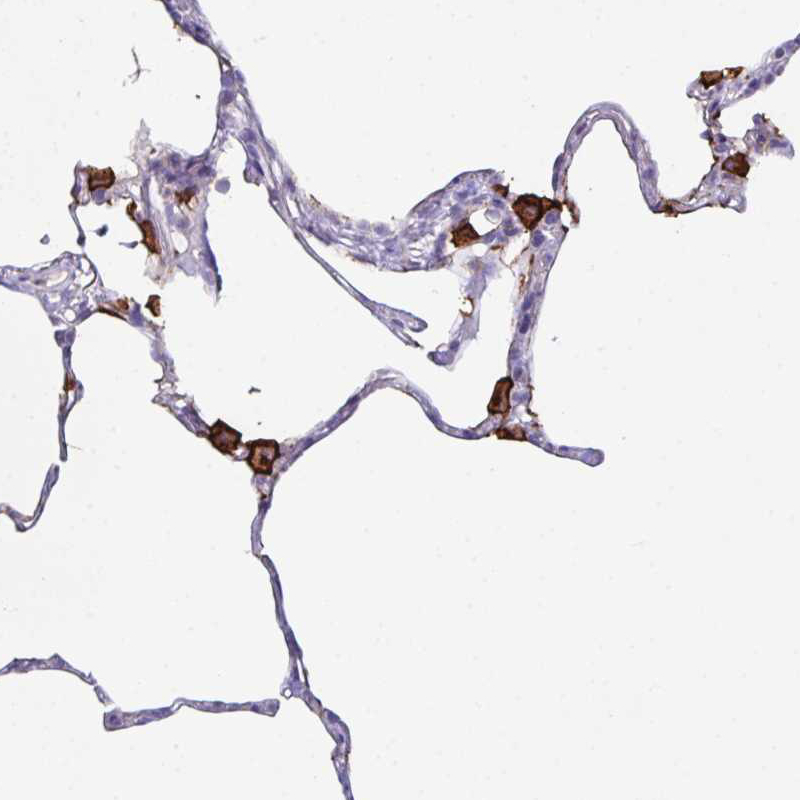

Immunohistochemistry analysis in human lung and pancreas tissues using HPA063793 antibody. Corresponding MARCO RNA-seq data are presented for the same tissues.